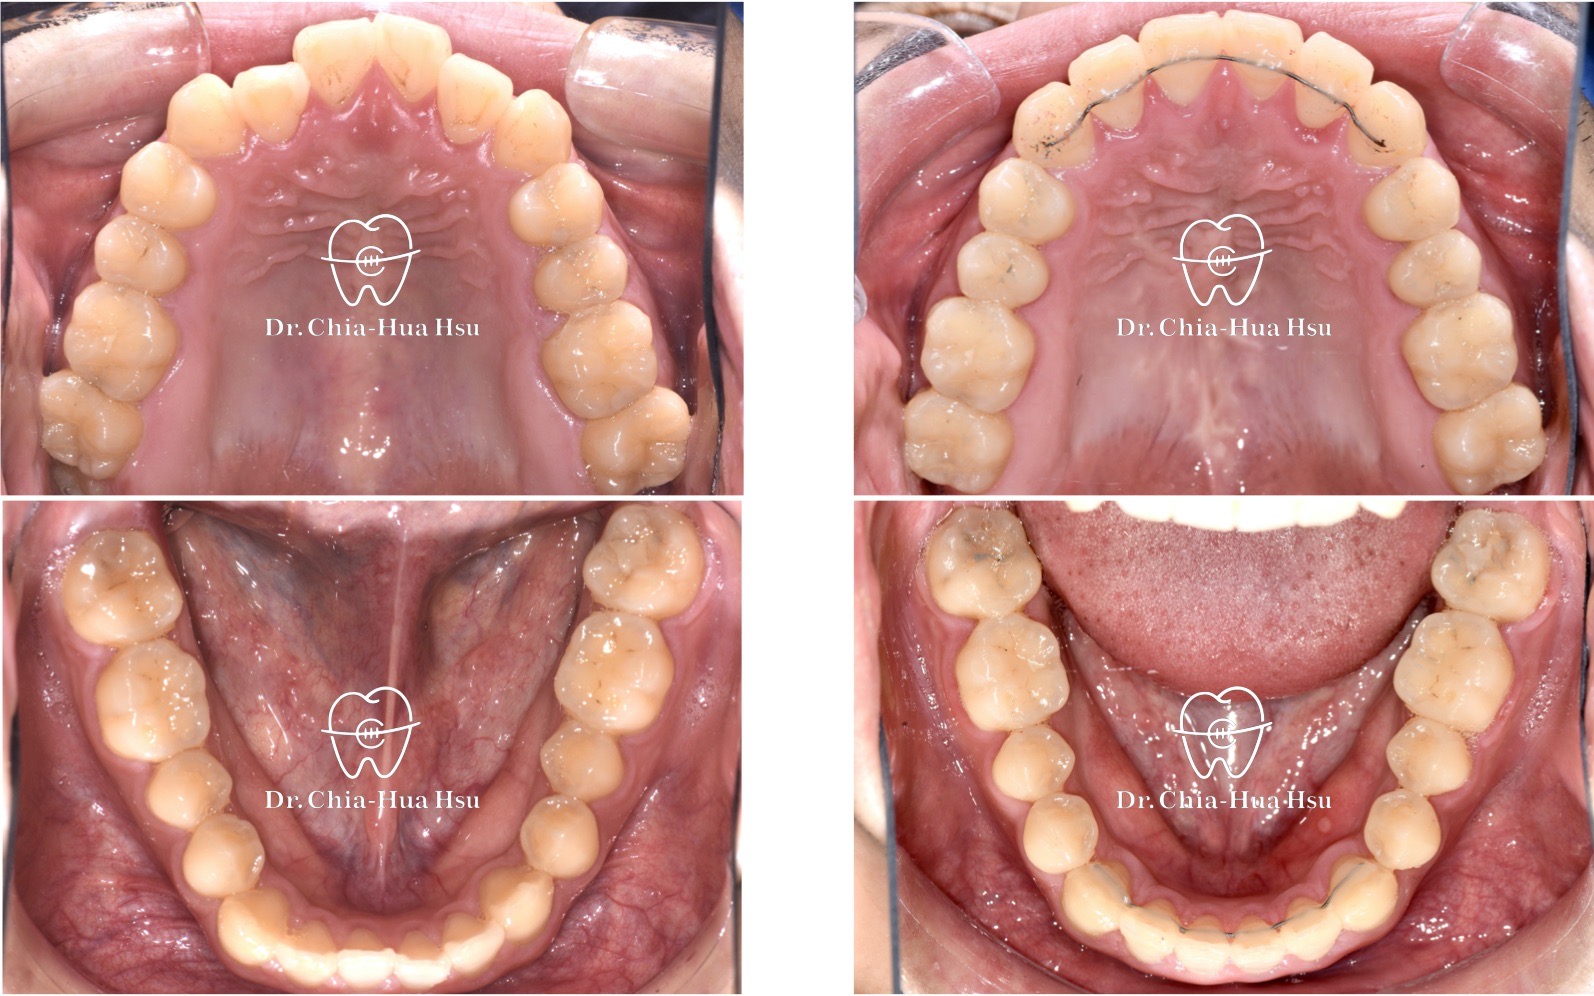

戽斗、錯咬

成人矯正 | 金屬矯正 | 非拔牙治療

• 病患主訴:前牙錯咬、不整齊,有戽斗臉型,但不想做正顎手術。

• 問題分析:患者是輕微的骨骼三類咬合(Skeletal Class III)、下巴過長(戽斗)、前牙錯咬以及齒列不整齊。

• 治療方式:使用傳統金屬矯正器,並搭配垂直向橡皮筋牽引(Vertical elastics)使牙齒萌出。

• 治療時間:2 年。

• 治療結果:門牙露出增加、齒列排齊 ; 下臉部高度微增使下巴順時針微量旋轉,以修飾戽斗臉型。

治療前

治療後